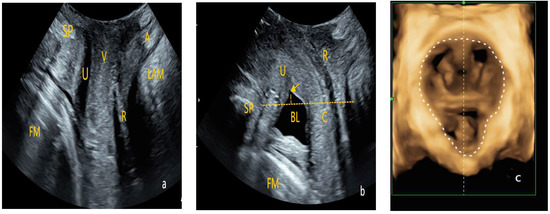

- Examination Method: After the patient emptied their bladder and bowels, they were positioned supine on the examination table with their legs flexed and mildly abducted in the lithotomy position. The specialized probe was wrapped and a large amount of disinfectant gel was applied to avoid air interference within the probe cover, ensuring good image quality. The probe was placed between the labia, and images of the pelvic floor in the mid-sagittal plane were obtained in three conditions—at rest, during maximal voluntary contraction, and during a Valsalva maneuver. The structures examined included the pubic symphysis, urethra, bladder, vagina, rectum, anal canal, and anorectal angle. Using the pubic symphysis as the central reference point, the sagittal plane images of the vagina, urethra, and anal canal were captured. Volume scanning was then performed, with appropriate adjustment of the selected region to collect two-dimensional and four-dimensional ultrasonographic images of the pelvic floor at rest, during maximal voluntary contraction, and during the Valsalva maneuver (Figure 2).